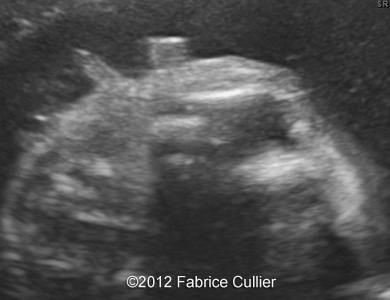

Image 2,3 : Coronal view of mouth and face at 28 weeks.

4a

4b